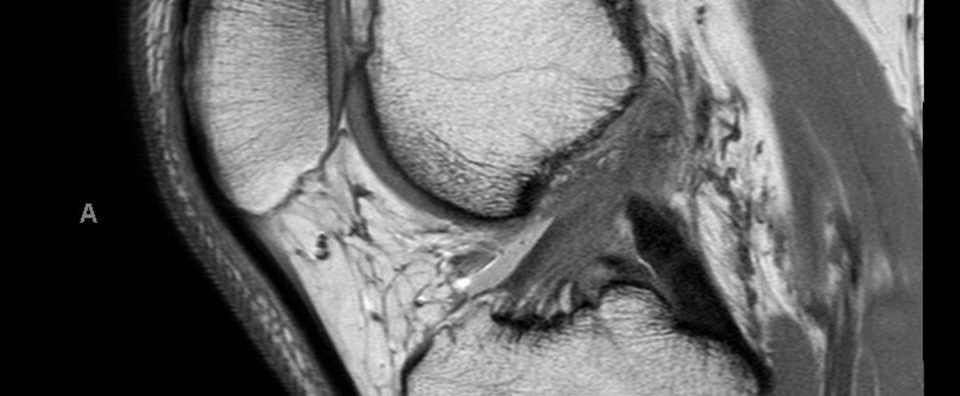

膝前十字靭帯 Acl 損傷の患者様へ スポーツ整形 山形徳洲会病院 整形外科

膝前十字靭帯損傷 整形外科 スポーツ診療科 順天堂医院